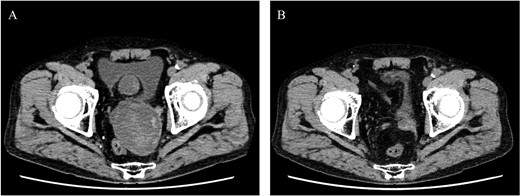

A 68-year-old male was admitted for the expansion of a left IIAA. He had undergone coiling of peripheral branches and stent graft placement in the left common iliac artery (CIA) 10 years prior. Eight years prior, an endoleak was detected between the left CIA and the left IIA. This led to the patient undergoing Y-grafting and disconnection of the CIA and IIAA. Contrast-enhanced computed tomography (CT) revealed a giant IIAA, with a maximum short diameter of 66 mm, and no signs of endoleak (Fig. 1). The aneurysm presented as a cluster of three separate lobes, resembling a dumpling-like structure.

Preoperative computed tomography imaging showing a giant left internal iliac artery aneurysm in a dumpling-like cluster with a maximum short diameter of 66 mm. A—Axial image, B—3D image. LIIAA, left internal iliac artery aneurysm.